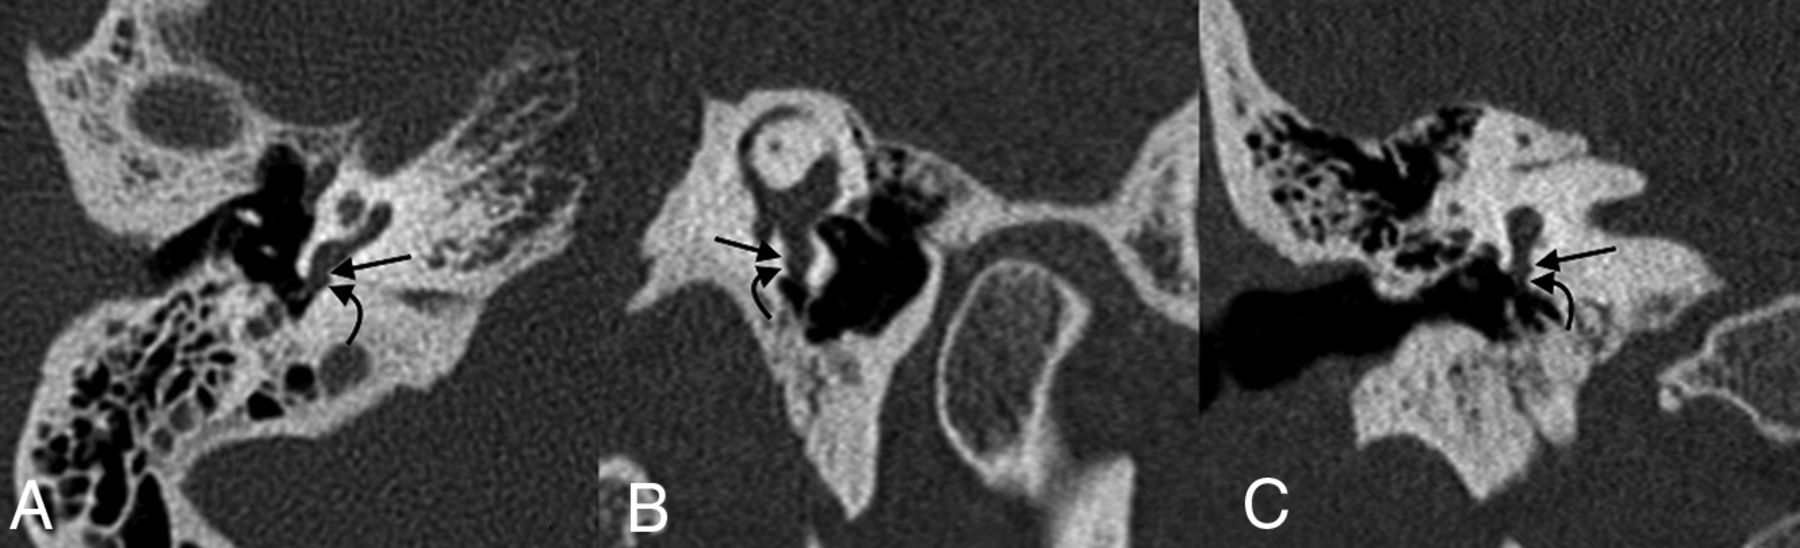

The round window is located along the posterior aspect of the cochlear promontory and measures 1.5–2.1 mm horizontally, 1.9 mm vertically, and 0.65 mm in thickness (Fig 1).1,5 The round window membrane is thicker along its edges and thinner in the middle and is made up of 3 layers: 2 epithelial layers facing the inner and middle ear, respectively, and connective tissue in the core.6 Contrary to its name, the shape of the round window is typically skewed, ovoid, and nonplanar according to a recent study.7 The round window niche is primarily defined by the relatively thin overhanging bone that naturally extends from the promontory. This overhanging bone may obscure complete direct visualization of the round window membrane during routine middle ear surgery and cochlear implantation (Fig 2).8 In addition, most ears have a thin layer of mucosa covering the round window membrane, often called a “pseudomembrane,” that blocks direct visualization of the window if not removed.

Normal round window anatomy. Axial (A), coronal (B), Stenvers (C), and Pöschl (D) images centered on the round window membrane (straight white arrows), situated between the basal turn of the cochlea (black arrows) and the round window niche of the middle ear (curved white arrows). The oval window is closely adjacent (dashed arrow).

Round window stenosis. A 52-year-old woman with profound bilateral hearing loss. Axial (A), coronal (B), and Pöschl (C) images of the right temporal bone demonstrate advanced stenosis of the round window (arrows).